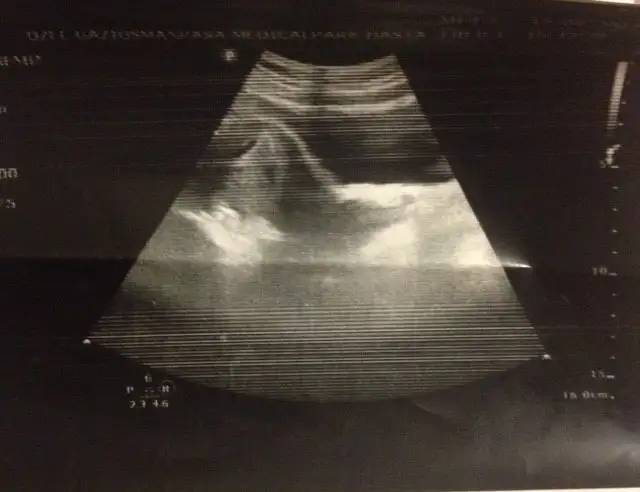

Burda da kız gibi :)) kesenin içinde sağ tarafa daha yakın.. bu da karından usg değilmiBu da tam 7+1 teyzesi

evet karından usg valla bizimki sürpriz olacak :) kıza da benzeten var erkeğe de :) ortalarda bir yerde sanki. allah hayırlısını versin hepimize :)Burda da kız gibi :)) kesenin içinde sağ tarafa daha yakın.. bu da karından usg değilmi

Evet canım karından usg :))Karından usg ise erkek gibi canım senin bebiş :)